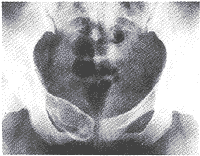

骨囊腫(UBC),又叫單純骨囊腫,其病變腔內充填為液體,四壁為薄的殼膜。單純性骨囊腫常發生於5到15歲的兒童,男性發病多於女性,比率約為2:1。病變部位多在長骨的乾骺端。最常見部位為肱骨近端,其次為股骨近端。活動性(active相對具有侵襲性的)骨囊腫靠近骨骺區,隨著兒童年齡增大,病灶會逐漸遠離骨骺,成為非活動性(inactive)。在年齡超過17歲的患者,病變會在非長管骨發生,如跟骨、骨盆等。

有經驗的骨腫瘤醫生僅憑X線平片就可以作出骨囊腫的臨床診斷。病變灶為邊界清晰的液性低密度灶,四壁為薄層的硬化灶殼。病變灶略向近骨骺的乾骺部位擴大。病灶非偏心性,也不破壞骨外殼,更不會突破骨質形成骨膜外反應骨,除非是在病理骨折後的癒合期。有時脫落的骨皮質成份落入囊腔中,X片顯示被稱為“落葉征”(FallenleaforFallenfragment)。當病灶發生在骨盆,CT掃描對病灶部位及囊腫形態的判斷有價值。MRI可以明確囊內富含的液性成分。骨ECT掃描表現為外周薄的濃集而中央病灶冷區。

3.X線攝片顯示長骨幹骺端有橢圓形密度均勻的透明陰影,病變局限,與正常骨質間有明顯界線,骨皮質膨脹變薄。